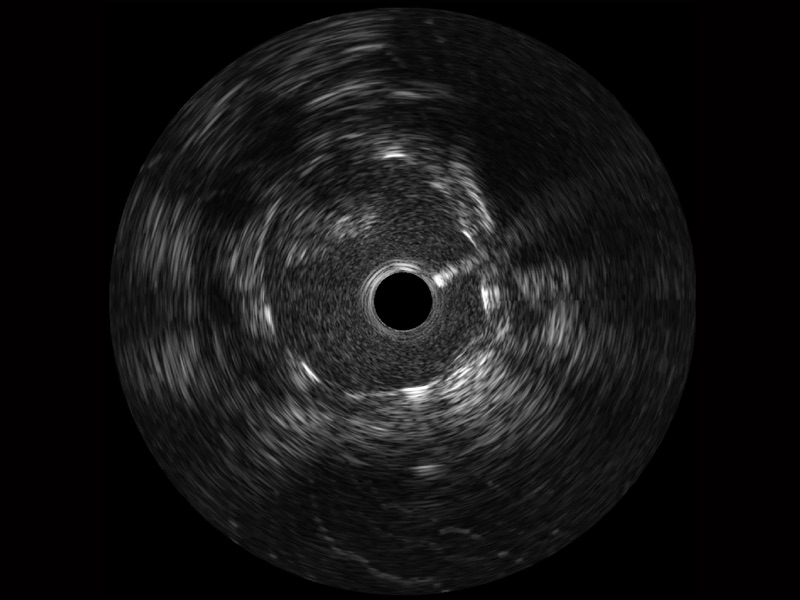

新葡的京集团8814检测站宽频IVUS图像

对比传统IVUS导管成像,新葡的京集团8814检测站宽频IVUS图像的近场支架梁显影更细腻,远场中膜外血管仍清晰可辨,兼顾远中近,兼顾分辨力与穿透深度